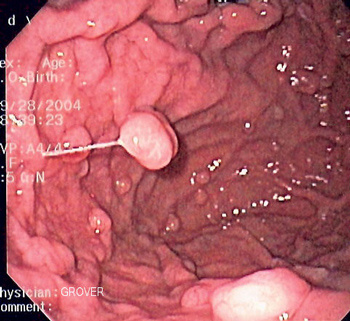

Полип ∅6 мм фундальных желёз тела  желудка 46-летней женщины,

предположительно также больной ГЭРБ*

Полип ∅6 мм фундальных желёз тела желудка 46-летней женщины, предположительно также больной ГЭРБ*